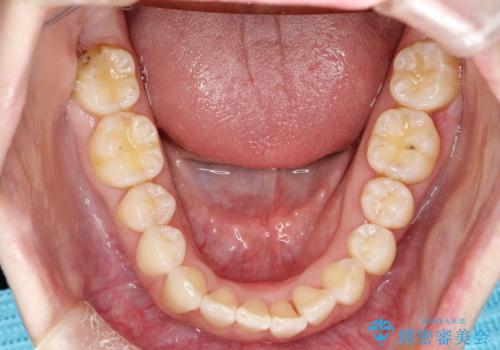

インビザライン ライトパッケージによる部分矯正治療 下の前歯のみの歯並び改善

- インビザライン ライトパッケージパーシャル(下顎のみ)

- 下の前歯の歯並びのみの改善をご希望されました。

インビザライン ライトパッケージ下顎のみ(1枚~14枚まで)での治療を行なっていきました。

マウスピース枚数 初回14枚 + 追加13枚

概ね7ヶ月で治療完了しました。

インビザラインのライトパッケージでは14枚までという枚数制限がありますが、限られた枚数の中で当院独自の工夫を随所に盛り込み、狙い通りの治療結果が得られました。